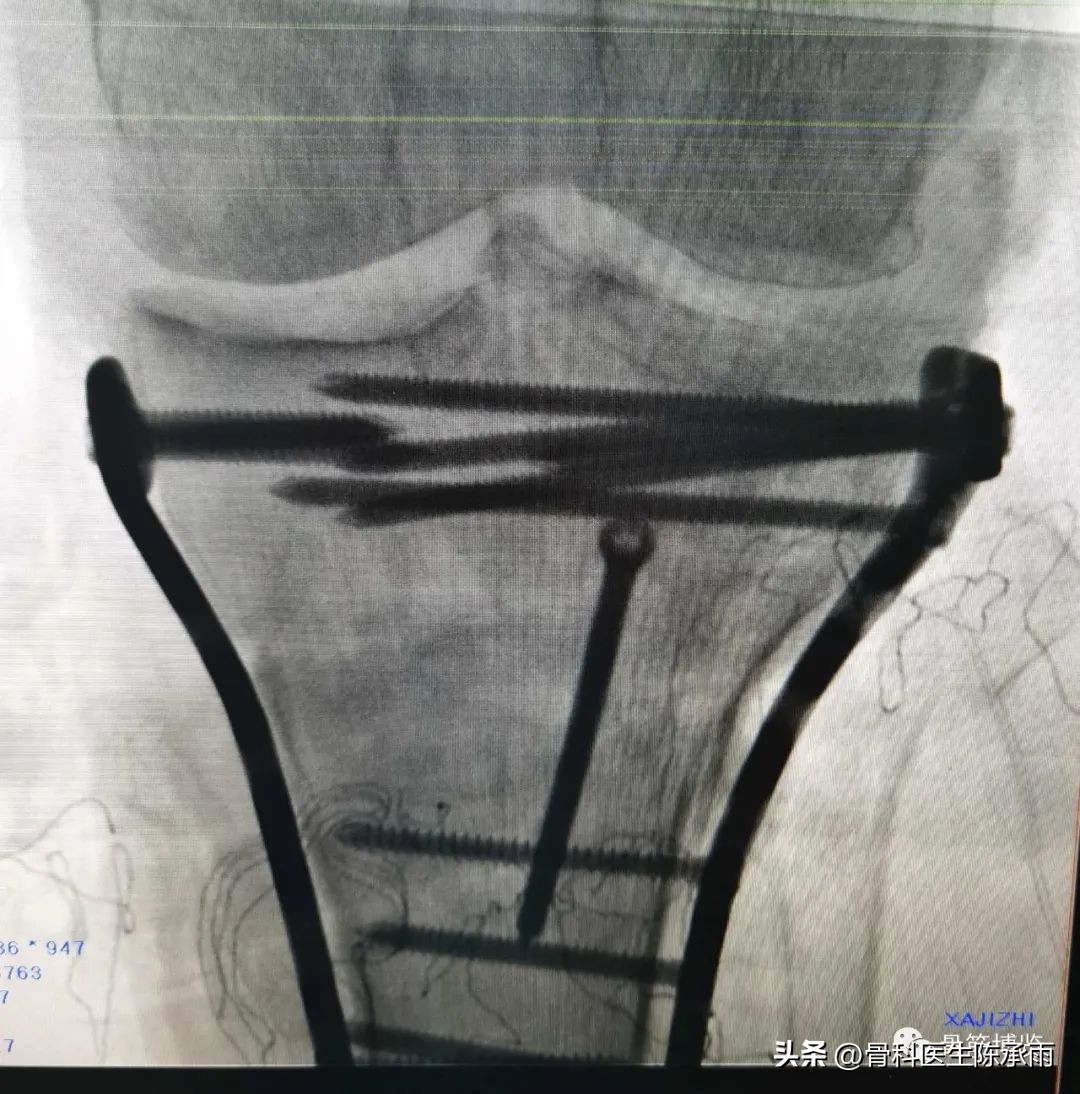

近段时间的胫骨平台骨折,没来得及详细整理

郓城县人民医院骨科诊疗技术飞速提升,开通了创伤中心绿色通道。现年手术病人达到1500余例,除常规手术外,微创手术迅速发展。关节镜,椎体成形,股骨粗隆闭合复位固定,髋膝关节置换,脊柱等手术在全市处于领先水平。